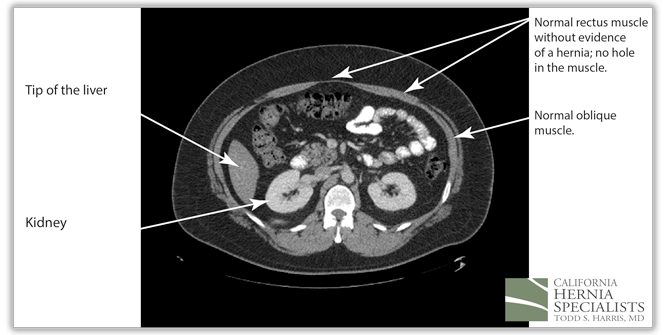

These 3 CT scan images show the patients muscle above the hernia where the muscle is normal, at the level of the hernia, and then below the hernia again where the muscle is normal.

The CAT scan image above shows normal muscles of the abdominal wall with no evidence of a hole, or a hernia.